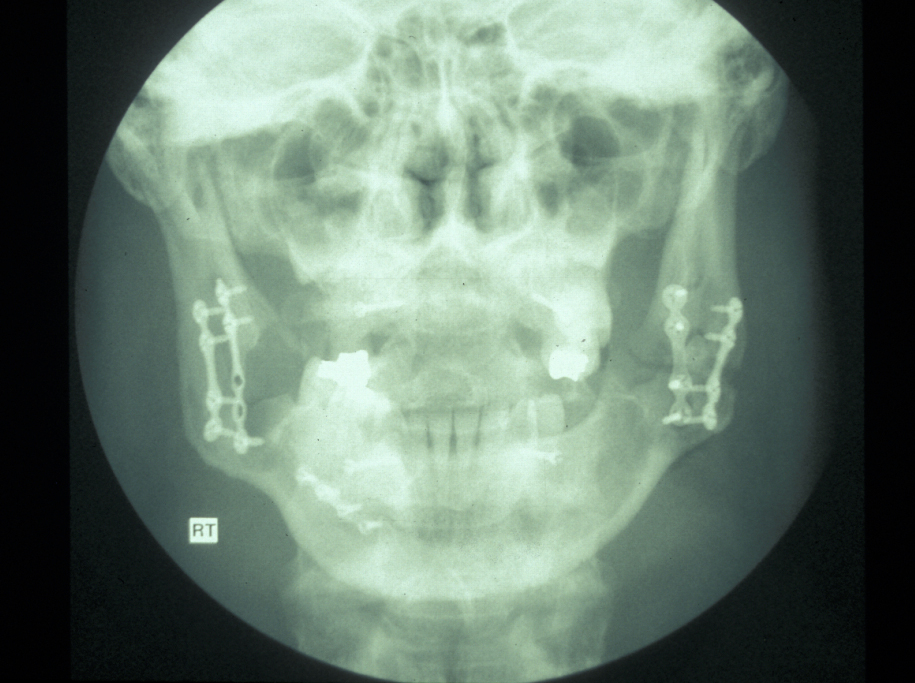

If midface fractures occur in conjunction with complex mandibular fractures and condylar fractures, it is imperative that a logical sequence of repair is taken. Mandibular condylar height must be restored to ensure the overall posterior facial height does not change. Once the condyle is repaired, the frontozygomatic suture and zygomatic arch can be repaired, thus setting the outer facial frame. The next fracture to approach is the lateral orbital wall, maxillary buttress and finally inner circle of medial orbital wall and piriform fossa. Adhering to this sequence of repair allows achieved logical sequence, rational stepwise reduction of the fractures and optimises the chances for a return to premorbid position; see Figure 20 for illustration.

Postoperative care

Postoperative analgesia, antibiotics and meticulous oral hygiene are required. Condylar height and midfacial position should be confirmed on postoperative radiographs. Skin sutures should be removed at five days, removal of coronal flap staples at seven days. Temporary IMF with elastic bands should be placed to reinforce the occlusal position for at least seven days. Soft diet is recommended to ensure the plates and the reduced fractures do not move. Contact sports should be avoided for approximately three months postoperatively.